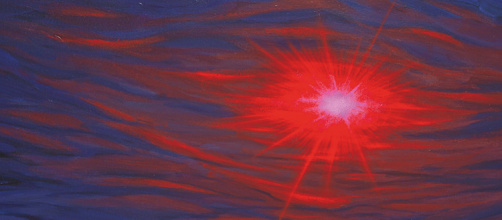

Soulager la douleur, en identifiant ses biomarqueurs